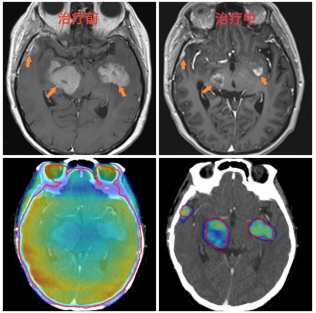

三周的系统治疗转瞬即逝,郝女士的身体迎来了质的飞跃。颅内病灶明显退缩,神经症状完全缓解,她不仅能稳稳地自主站立,还能一步步在病房里行走,步伐虽慢,却格外坚定。

面对郝女士的状况,主任王建华带领放疗科团队迅速投入工作,第一时间为她制定了个体化治疗方案。考虑到郝女士体力衰弱,无法配合常规体位固定,团队启用了西门子GoSim大孔径定位CT。宽大的孔径设计让她在定位时少了诸多不适,有效减少了身体移动带来的误差,而设备捕捉到的高分辨率影像,也为后续靶区勾画和剂量计算提供了清晰可靠的依据。

治疗阶段,医科达VersaHD高端直线加速器正式“登场”。它能灵活塑造照射野,让高剂量射线精准瞄准肿瘤,同时最大程度避开周围正常脑组织,既保证了疗效,又降低了副作用。

更贴心的是,每次治疗前,医院都会通过全程图像引导技术,将实时扫描图像与定位CT比对,校正哪怕微小的体位偏差,确保每一次照射都精准无误。